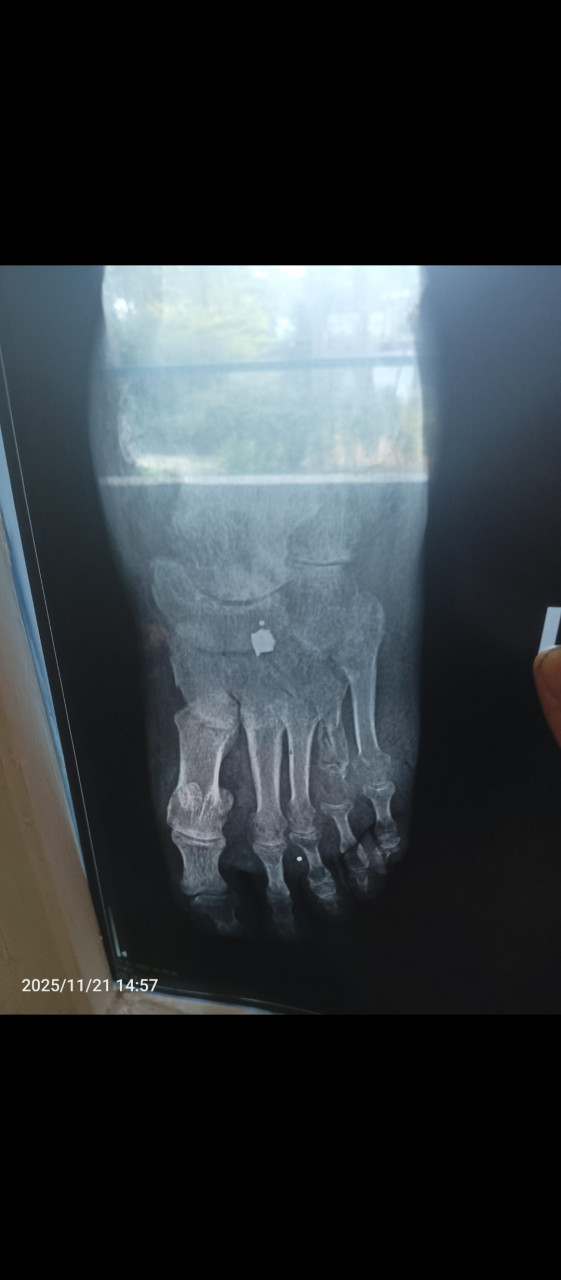

После перелома 4 плюсневой кости с смещением отломков и снятия гипса болит область перелома и большой палец, имеется отёчность.

Здравствуйте. Снимки низкого качества, поэтому детали смещения оценить сложно. После перелома плюсневой кости боль и отёк могут сохраняться несколько недель, особенно если было смещение. Но если боль усиливается или сохраняется долго, нужно повторное рентген-обследование и очный осмотр травматолога, чтобы исключить неполное сращение или посттравматический отёк.